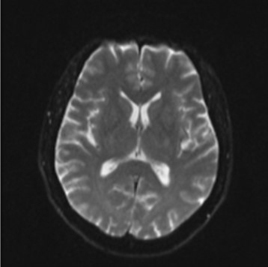

圖一、正常腦部核磁共振影像